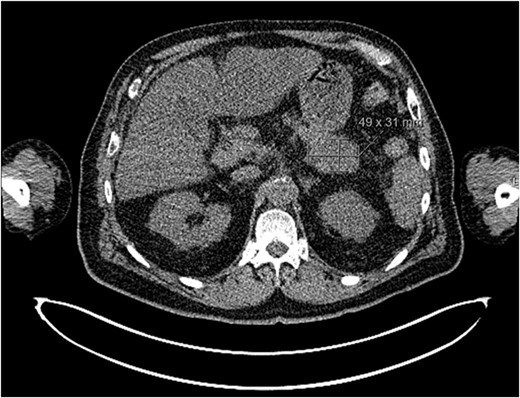

Post-review, he was listed for an urgent biopsy under local anaesthetic. Histology showed well-to-moderately differentiated adenocarcinoma, with the likely primary being upper gastrointestinal or pancreatic in origin. Positive immunostaining was noted for CK7 and negative for p63, TTF-1, Napsin, CK20 and PSA. Magnetic resonance imaging (MRI) of the face and neck showed a 2.6-cm lesion on the chin invading subcutaneous tissues, with no mandibular involvement (Fig. 1). Due to the nature of the histology results, he underwent a positron emission tomography(PET)-computed tomography (CT) scan, which showed a cystic area in the pancreatic tail, alluding to a pancreatic adenocarcinoma primary. Widespread metastases noted included multifocal liver metastases, peritoneal lymph node, muscle and bony involvement (Figs 2–4).